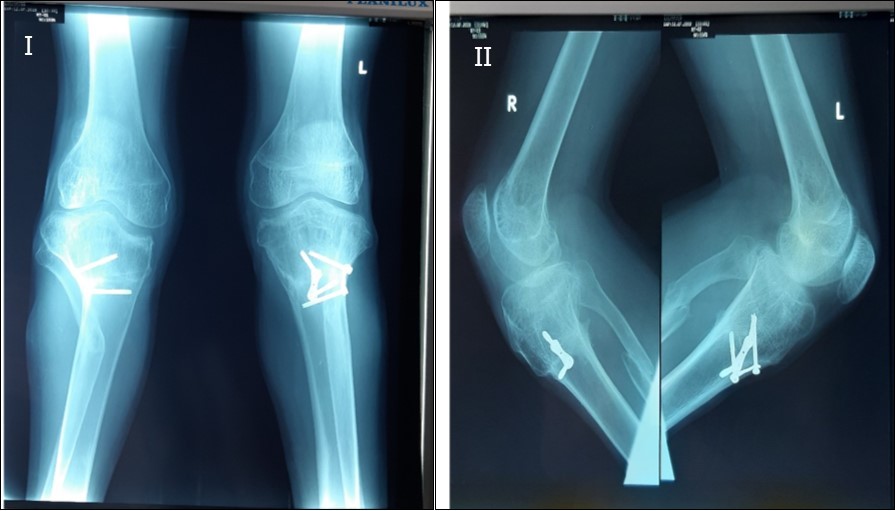

There was satisfactory correction of his deformities at his last out-patient visit, 2 years post operatively, with acceptable mobility of the knees, 0- 120 degrees of passive knee motion. Figure 7.

The patient is ambulatory and now has painless knees, a remarkable improvement in gait, no lateral knee thrust, no limb length discrepancy and is able to participate in activities at a higher level and is cosmetically optimised. Figure 8.

Figure 8.X-ray of both knees of the patient anteroposterior view, I, and lateral view II, 2yrs post operatively showing correction of the bilateral tibia vara with 8-plate and screws in situ.